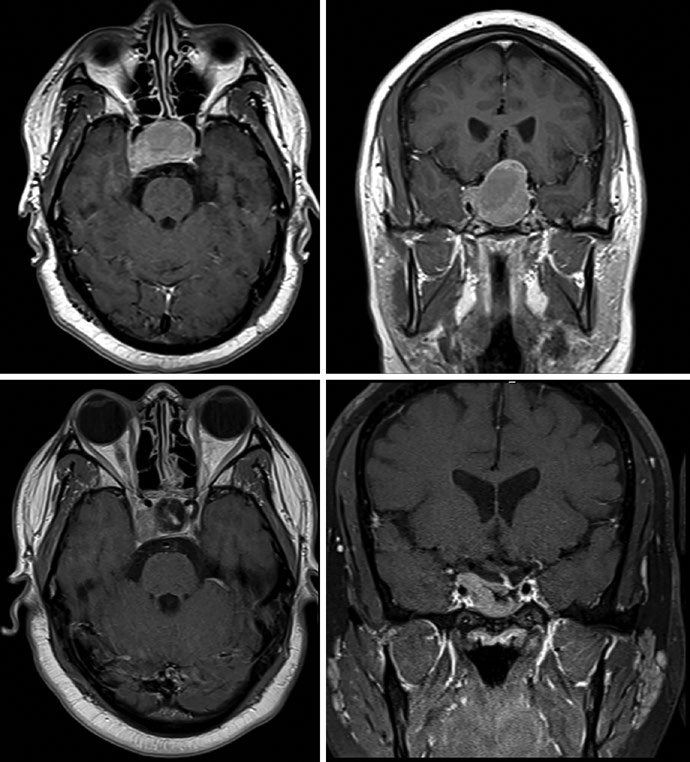

Adenomas não funcionantes são tipicamente tratados com SRS, HSRT ou RT convencional fracionada no cenário adjuvante ou de resgate após ressecção. Adenomas funcionantes podem receber terapia hormonal ou cirurgia antes de se considerar radioterapia. Imagens de RM de alta resolução com cortes finos nos planos coronal e sagital são essenciais para delinear os volumes-alvo. Os adenomas são melhor visualizados na fase precoce do gadolínio dinâmico, aparecendo como lesão hipointensa contra o fundo hiperintenso da glândula hipofisária normal.